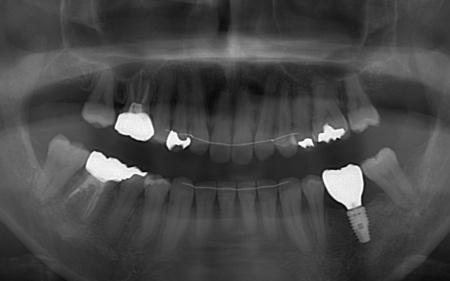

拝見したところ、左下奥歯(第1大臼歯)は以前、歯根分割処置が行われていました。

しかし残していた歯根の状態も悪化しており、治療しても温存は困難と判断しました。

左下奥歯はこのまま放置すると細菌感染を引き起こすため抜歯が必要なこと、抜歯後に歯を補うため人工歯根を利用したインプラント治療を提案し、同意いただきました。

③矯正治療と並行して左下奥歯を抜歯し、インプラント治療を行う。

インプラントを支えるための骨の量が十分でないため、人工材料を用いて骨を再生させる骨造成(GBR)を併用しながらインプラントを埋入する。

インプラントがしっかりと骨に定着したことを確認してから、人工歯を取り付ける。